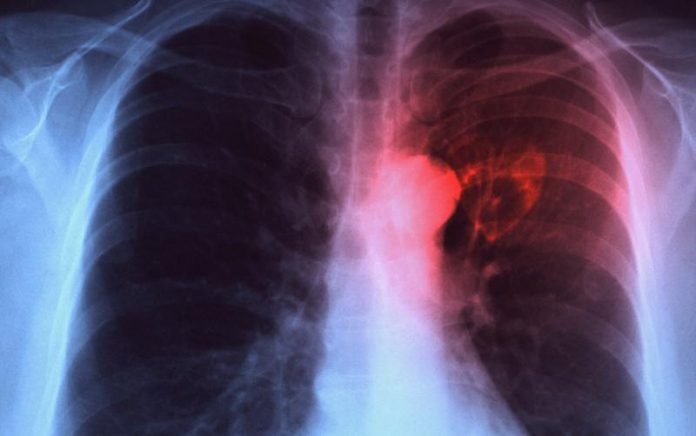

JAKARTA – Perhimpunan Dokter Paru Indonesia (PDPI) menyatakan penanggulangan untuk penyakit Tuberkulosis (TBC) di Indonesia harus menghadapi sejumlah tantangan yang cukup kompleks untuk bisa mencapai target eliminasi Tuberkulosis 2030.

“Tuberkulosis masih menjadi ancaman kesehatan dunia. Pascapandemi (COVID-19), terjadi peningkatan kasus Tuberkulosis di Indonesia, sehingga pada tahun 2022 Indonesia menempati peringkat kedua negara dengan kasus TB tertinggi di dunia setelah India,” kata Sekretaris Pokja Infeksi PDPI Irawaty Djaharuddin dalam konferensi pers “Yes We Can End TTuberkulosis” yang diikuti secara daring di Jakarta, Jumat lalu.

Ira menyampaikan salah satu tantangan yang menjadi kendala di lapangan adalah rendahnya angka penemuan kasus. Untuk itu, lanjutnya, pemerintah dan pihak terkait harus lebih meningkatkan pengetahuan masyarakat terkait gejala TBC melalui edukasi dan menguatkan pelacakan kasus.

Tantangan lain yang dihadapi adalah angka keberhasilan pengobatan yang belum mencapai target. Hal ini dapat berhasil jika pengobatan pasien Tuberkulosis ditunjang oleh pengobatan yang tepat dari tenaga kesehatan, ketersediaan obat sesuai standar, kepatuhan pasien, tata laksana efek samping obat yang memadai, dan pemanfaatan Video Observed Therapy (VOT) atau sistem pendukung penting lain sebagai alternatif pilihan untuk menunjang keberhasilan pengobatan.

Tantangan selanjutnya adalah angka morbiditas dan mortalitas TBC dengan penyulit seperti komorbid. Oleh karenanya Ira menilai edukasi menjadi hal yang sangat penting bagi masyarakat untuk mengetahui Tuberkulosis yang berat, Tuberkulosis yang terlambat diobati, serta Tuberkulosis dengan komplikasi yang menyebabkan kematian.